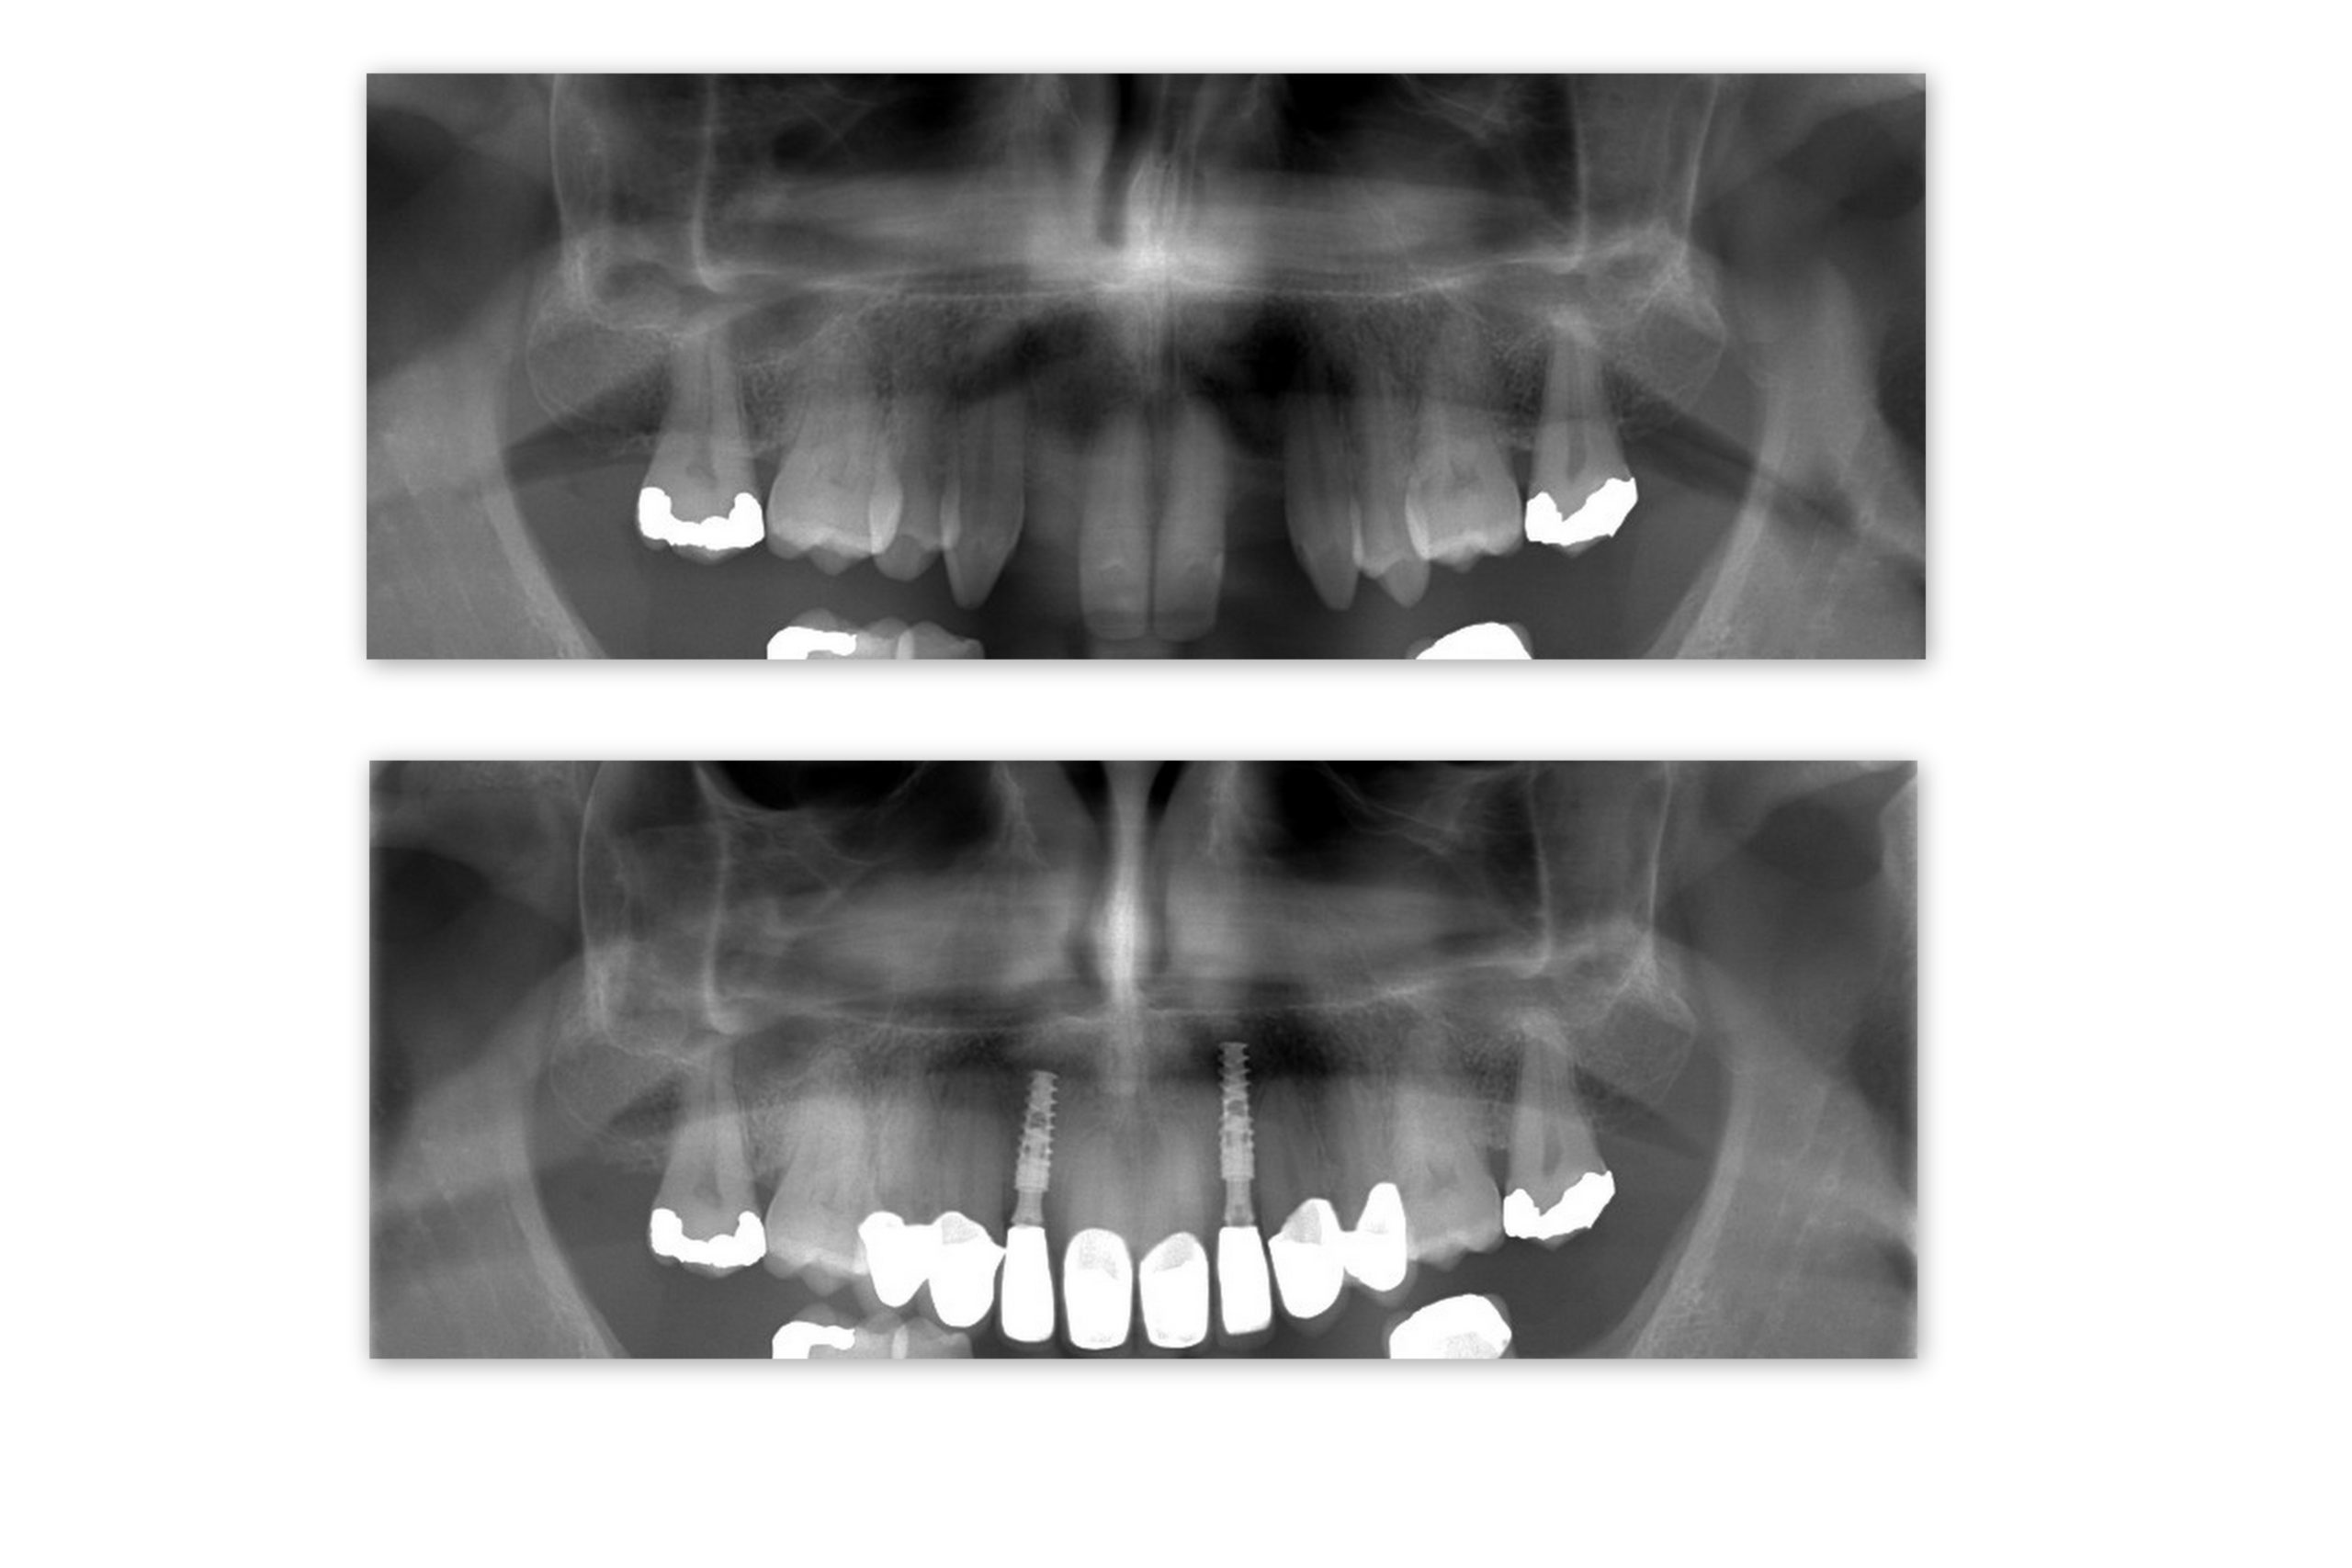

During the free initial consultation (learn more HERE) we made 2 treatment plans for Karl – one for the upper jaw and one for the lower jaw. Karl decided to proceed with his upper jaw – 2 dental implants for UL2 and UR2 (12 and 22) and 6 ceramic crowns for his front teeth.

After a painless surgery we provided him with temporary healing abutments and temporary crowns and he could fly back home.

After a 3 month healing period he came back to finish his dental implant treatment. Also, we reshaped his 6 front teeth and fit dental crowns onto them. Not only did he get rid of the retainer, but also he has this brilliant Hollywood look now!